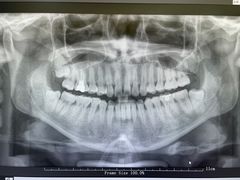

• 牙博士口腔品牌连锁(杨浦店)

• -牙博士口腔品牌连锁(杨浦店)